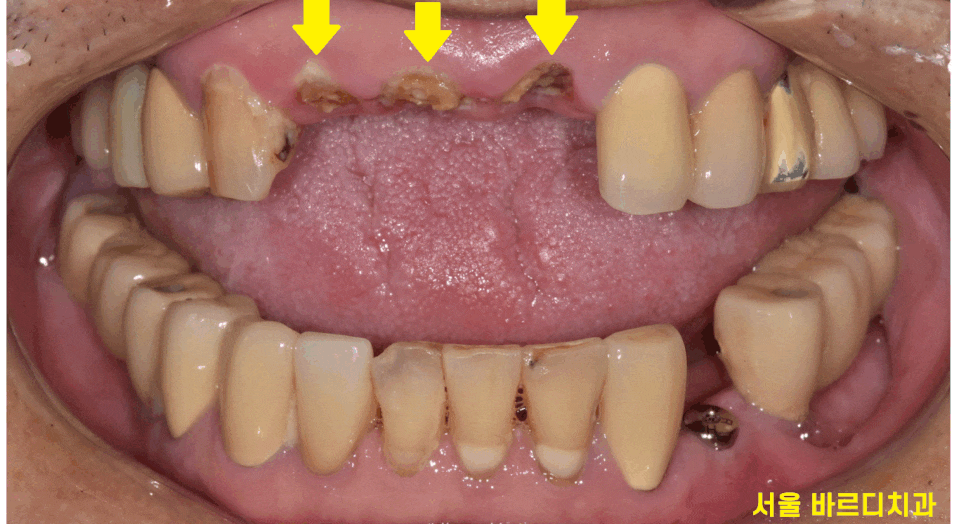

앞니 3개가 완전히 부러졌습니다.

사고 발생입니다.

3개의 부러진 앞니

기존에 신경치료 후 기둥까지 보강하여

씌운 치아였는데요.

기존에 치료 이유를 알 수는 없지만

충치가 심했다거나

남아있는 치아의 양이 얼마 되지 않아

기둥까지 심어 치아를 보강하여

치료했던 모양입니다.

가뜩이나 약한 치아인데 넘어지면서

치아에 충격이 제대로 갔네요ㅠㅠ